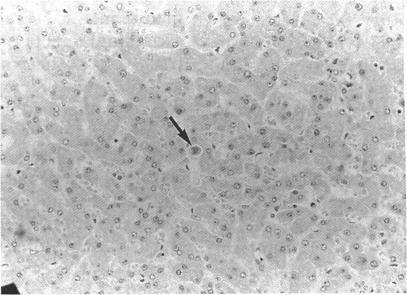

Disseminated cytomegalovirus infection.

Genitourin Med. 1992 Apr;68(2):75-9. doi: 10.1136/sti.68.2.75.